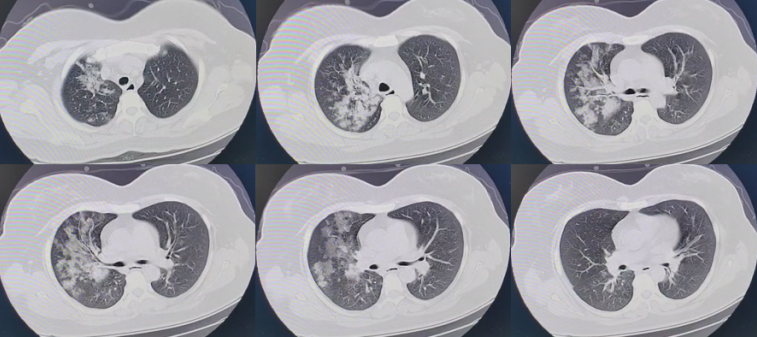

患者第二份胸部CT(12月26日,D16

患者的炎症指标好转,但最能反映病变严重程度的影像反而加重,而且这种影像特点无法用继发感染(细菌/真菌感染)解释。为什么病情(影像及氧合)会加重?我们分析认为问题可能在于抗炎治疗,包括抗炎治疗时机、抗炎治疗药物选择及剂量。

首先,在RECOVERY研究中,给予患者抗炎治疗的时间为起病后5~13天(平均8~9天),中日医院抗炎的时间为起病后9~14天(平均11天),抗炎时间晚于RECOVERY研究,这可能解释为何患者经规范治疗后仍病情进展。所以,我们能否早期应用抗炎,如在居家/养老院、急诊/门诊、普通病房使用激素等抗炎药物很重要。

其次,激素剂量可能存在一定问题。对于重症患者,常规给予地塞米松6 mg/d。但在纳入中重度ARDS患者的CoDEX研究中,地塞米松剂量为10 mg/d[5]。所以,对于ICU患者,尤其是气管插管患者,根据体重大小,可选择地塞米松6~10 mg/d。

再次,联合治疗可能也需要优化。目前我们联合治疗的药物有两个,分别是巴瑞替尼和托珠单抗,巴瑞替尼的价格较托珠单抗更便宜,所以我们早期会选择巴瑞替尼。关于巴瑞替尼的研究—COV-BARRIER研究[6],其结果也显示患者的病死率有下降,但需要注意的是,该研究排除了有创机械通气及正在使用免疫抑制剂的患者。另一项关于托珠单抗的研究纳入ICU后早期接受高级呼吸支持(有创通气/无创通气/经鼻高流量)或心血管(使用升压药或强心药)器官支持的患者[7]。所以巴瑞替尼和托珠单抗的应用人群不同。此外,托珠单抗是静脉用药,而巴瑞替尼是口服药物。所以,目前我们更倾向于使用托珠单抗,其起效更快。